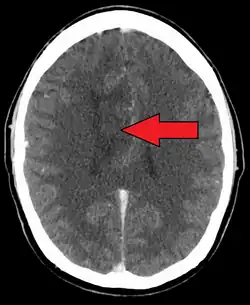

| A oligoastrocytoma on CT | |

An X-ray computed tomography (CT) or magnetic resonance imaging (MRI) scan is necessary to characterize the anatomy of this tumor as to size, location, and its homogeneity and heterogeneity. However, final diagnosis of this tumor, like most tumors, relies on histopathologic examination (biopsy examination).[4]

If resected, the surgeon will remove as much of this tumor as possible without disturbing eloquent regions of the brain such as the speech–Broca's area and Wernicke's area–and motor cortexes and other critical brain structure. Thereafter, treatment may include chemotherapy and radiation therapy of doses and types ranging based upon the patient's needs. Subsequent MRI examination are often necessary to monitor the resection margin.